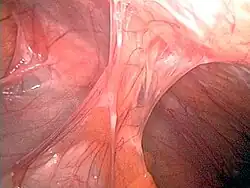

| Adhesions formed following appendectomy |

Adhesions are fibrous bands that form between tissues and organs,[1] often as a result of irritation of internal surfaces during surgery, infections or trauma. They may be thought of as internal scar tissue that connects tissues not normally connected.